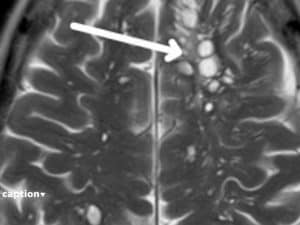

Il caso è stato segnalato dalla rivista scientifica American Journal of Case Reports. Il paziente, 52enne, lamentava continue emicranie. Si è sottoposto ad una TAC ed è arrivato il disgustosissimo responso.